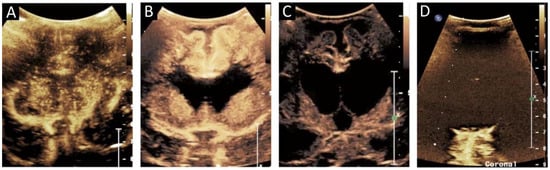

Figure 5.

(A) Ultrasound with color microvascular imaging in a 6 day old, former 32 week 2 day infant with multiple congenital anomalies including absence of the septum pellucidum. Overall reduced cortical and deep gray nuclei microvascular flow is observed. (B) Ultrasound with color microvascular imaging of a 51 day old, former term infant with congenital hydrocephalus. Overall increased microvascular perfusion is seen throughout the cortex, white matter, and deep gray matter compared to the infant in (A). The significance of these and similar findings has yet to be elucidated and may be of import for clinical management and prognostication.

Figure 6.

(A) Grayscale and (B) color microvascular imaging ultrasound a 13 day old, former 33 week 5 day infant with congenital heart disease and hypoxic respiratory failure on extracorporeal membrane oxygenation with seizures. Elevated flow is seen within the deep gray matter. This may reflect perfusion alterations in the setting of seizure, dysfunctional autoregulation, and/or evolving injury.